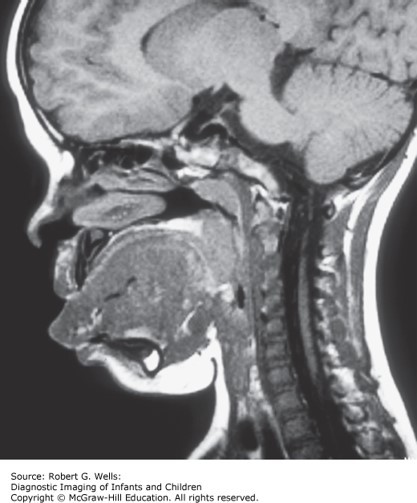

She is noted to have facial hemangiomata, pits on the backs of her ear helices, and double creases in her earlobes. Abdominal ultrasound reveals enlarged, lobulated kidneys.

The correct answer is A. The child has Beckwith–Wiedemann syndrome. These patients generally do quite well cognitively unless there are problems with untreated hypoglycemia in infancy. The other features on the list are possible complications of Beckwith–Wiedemann, but have not been associated with the development of cognitive impairment. (Chapter 176: "Syndromes of Multiple Congenital Anomalies/Dysplasias: Introduction" and Chapter 177: "Craniofacial Disorders: Introduction")

Photo: Wells RG. Diagnostic Imaging of Infants and Children; 2015.